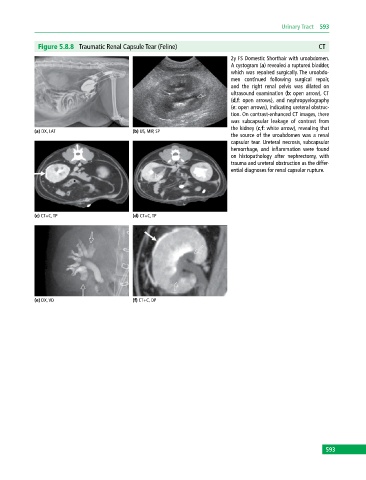

Figure 5.8.8 Traumatic Renal Capsule Tear (Feline) CT

2y FS Domestic Shorthair with uroabdomen.

A cystogram (a) revealed a ruptured bladder,

which was repaired surgically. The uroabdo-

men continued following surgical repair,

and the right renal pelvis was dilated on

ultrasound examination (b: open arrow), CT

(d,f: open arrows), and nephropyelography

(e: open arrows), indicating ureteral obstruc-

tion. On contrast‐enhanced CT images, there

was subcapsular leakage of contrast from

the kidney (c,f: white arrow), revealing that

the source of the uroabdomen was a renal

capsular tear. Ureteral necrosis, subcapsular

hemorrhage, and inflammation were found

on histopathology after nephrectomy, with

trauma and ureteral obstruction as the differ-

ential diagnoses for renal capsular rupture.